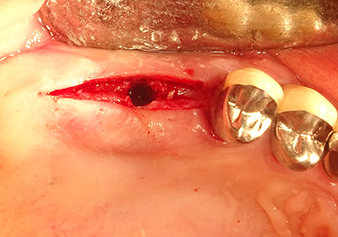

49-летняя пациентка, некурящая и не имеющая ничего примечательного в общей истории болезни, была направлена в нашу хирургическую стоматологическую клинику для хирургического удаления зуба 16 и последующей имплантации. После удаления зуба пациентка перенесла синусит в легкой форме, в результате чего мы сначала выждали шесть месяцев перед проведением операции. Остаточная высота кости при запланированном положении имплантата составляла 3-4 мм (рис. 1 и 2).